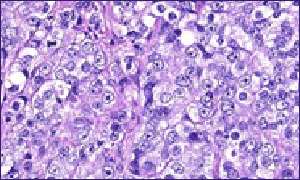

Prostate cancer

Prostate cancer affects 22,000 men a year in the UK